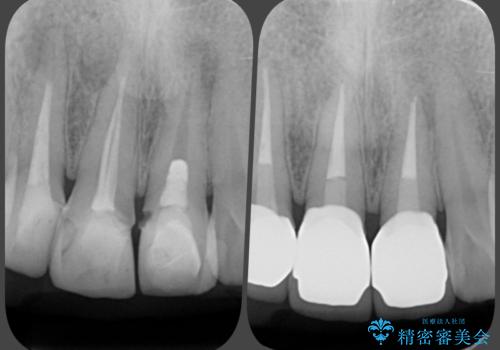

上下の歯は、上顎の歯が相対的に前に位置する咬合関係で押し出されるように前歯に角度がついている状態です。

咬合関係の改善、前歯の角度、がたつきを改善するため、マイクロインプラントを用いて上顎の奥歯を後方へ移動させていきます。